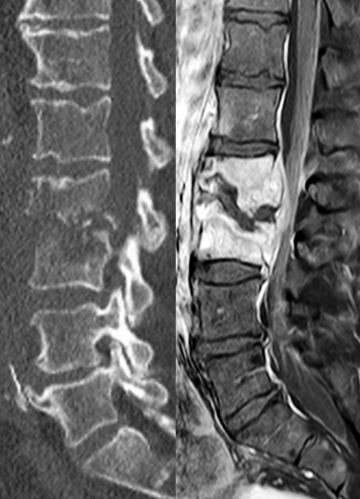

Rückenschmerzen können viele Ursachen haben und nicht in jedem Fall muss dafür eine Entzündung als Auslöser der Grund sein. Daher werden diese Schmerzen oftmals als „nicht spezifisch“ klassifiziert. Liegt jedoch der Verdacht einer Spondylodiszitis nahe, so ist man zur Diagnosesicherung auf eine apparative Diagnostik angewiesen. Hierzu zählen: Laboruntersuchungen, Nachweisversuche von Bakterien im Blut (Blutkulturen) sowie bildgebende Verfahren wie Röntgen, MRT und CT (Alternative zu MRT). Zur Verhinderung von Folgeschäden muss eine Herzultraschalluntersuchung (Echokardiografie) vorgenommen werden.

Auf den Bildern ist eine Wirbelkörperentzündung der Lendenwirbelkörper 2 und 3 zu sehen. Beim linken Bild zeigt das CT eine Zerstörung des Knochens und ein beginnendes „Ineinandersinken“ der Wirbelkörper. Das MRT zeigt auf der rechten Seite eine deutliche Signaländerung der Wirbelkörper (heller) als Ausdruck eines entzündlichen Prozesses. Zusätzlich wird ein Abszess im Rückenmarkskanal sichtbar, welcher den Rückenmarkskanal einengt und zu Ausfallerscheinungen führt (beginnende Querschnittsymptomatik).